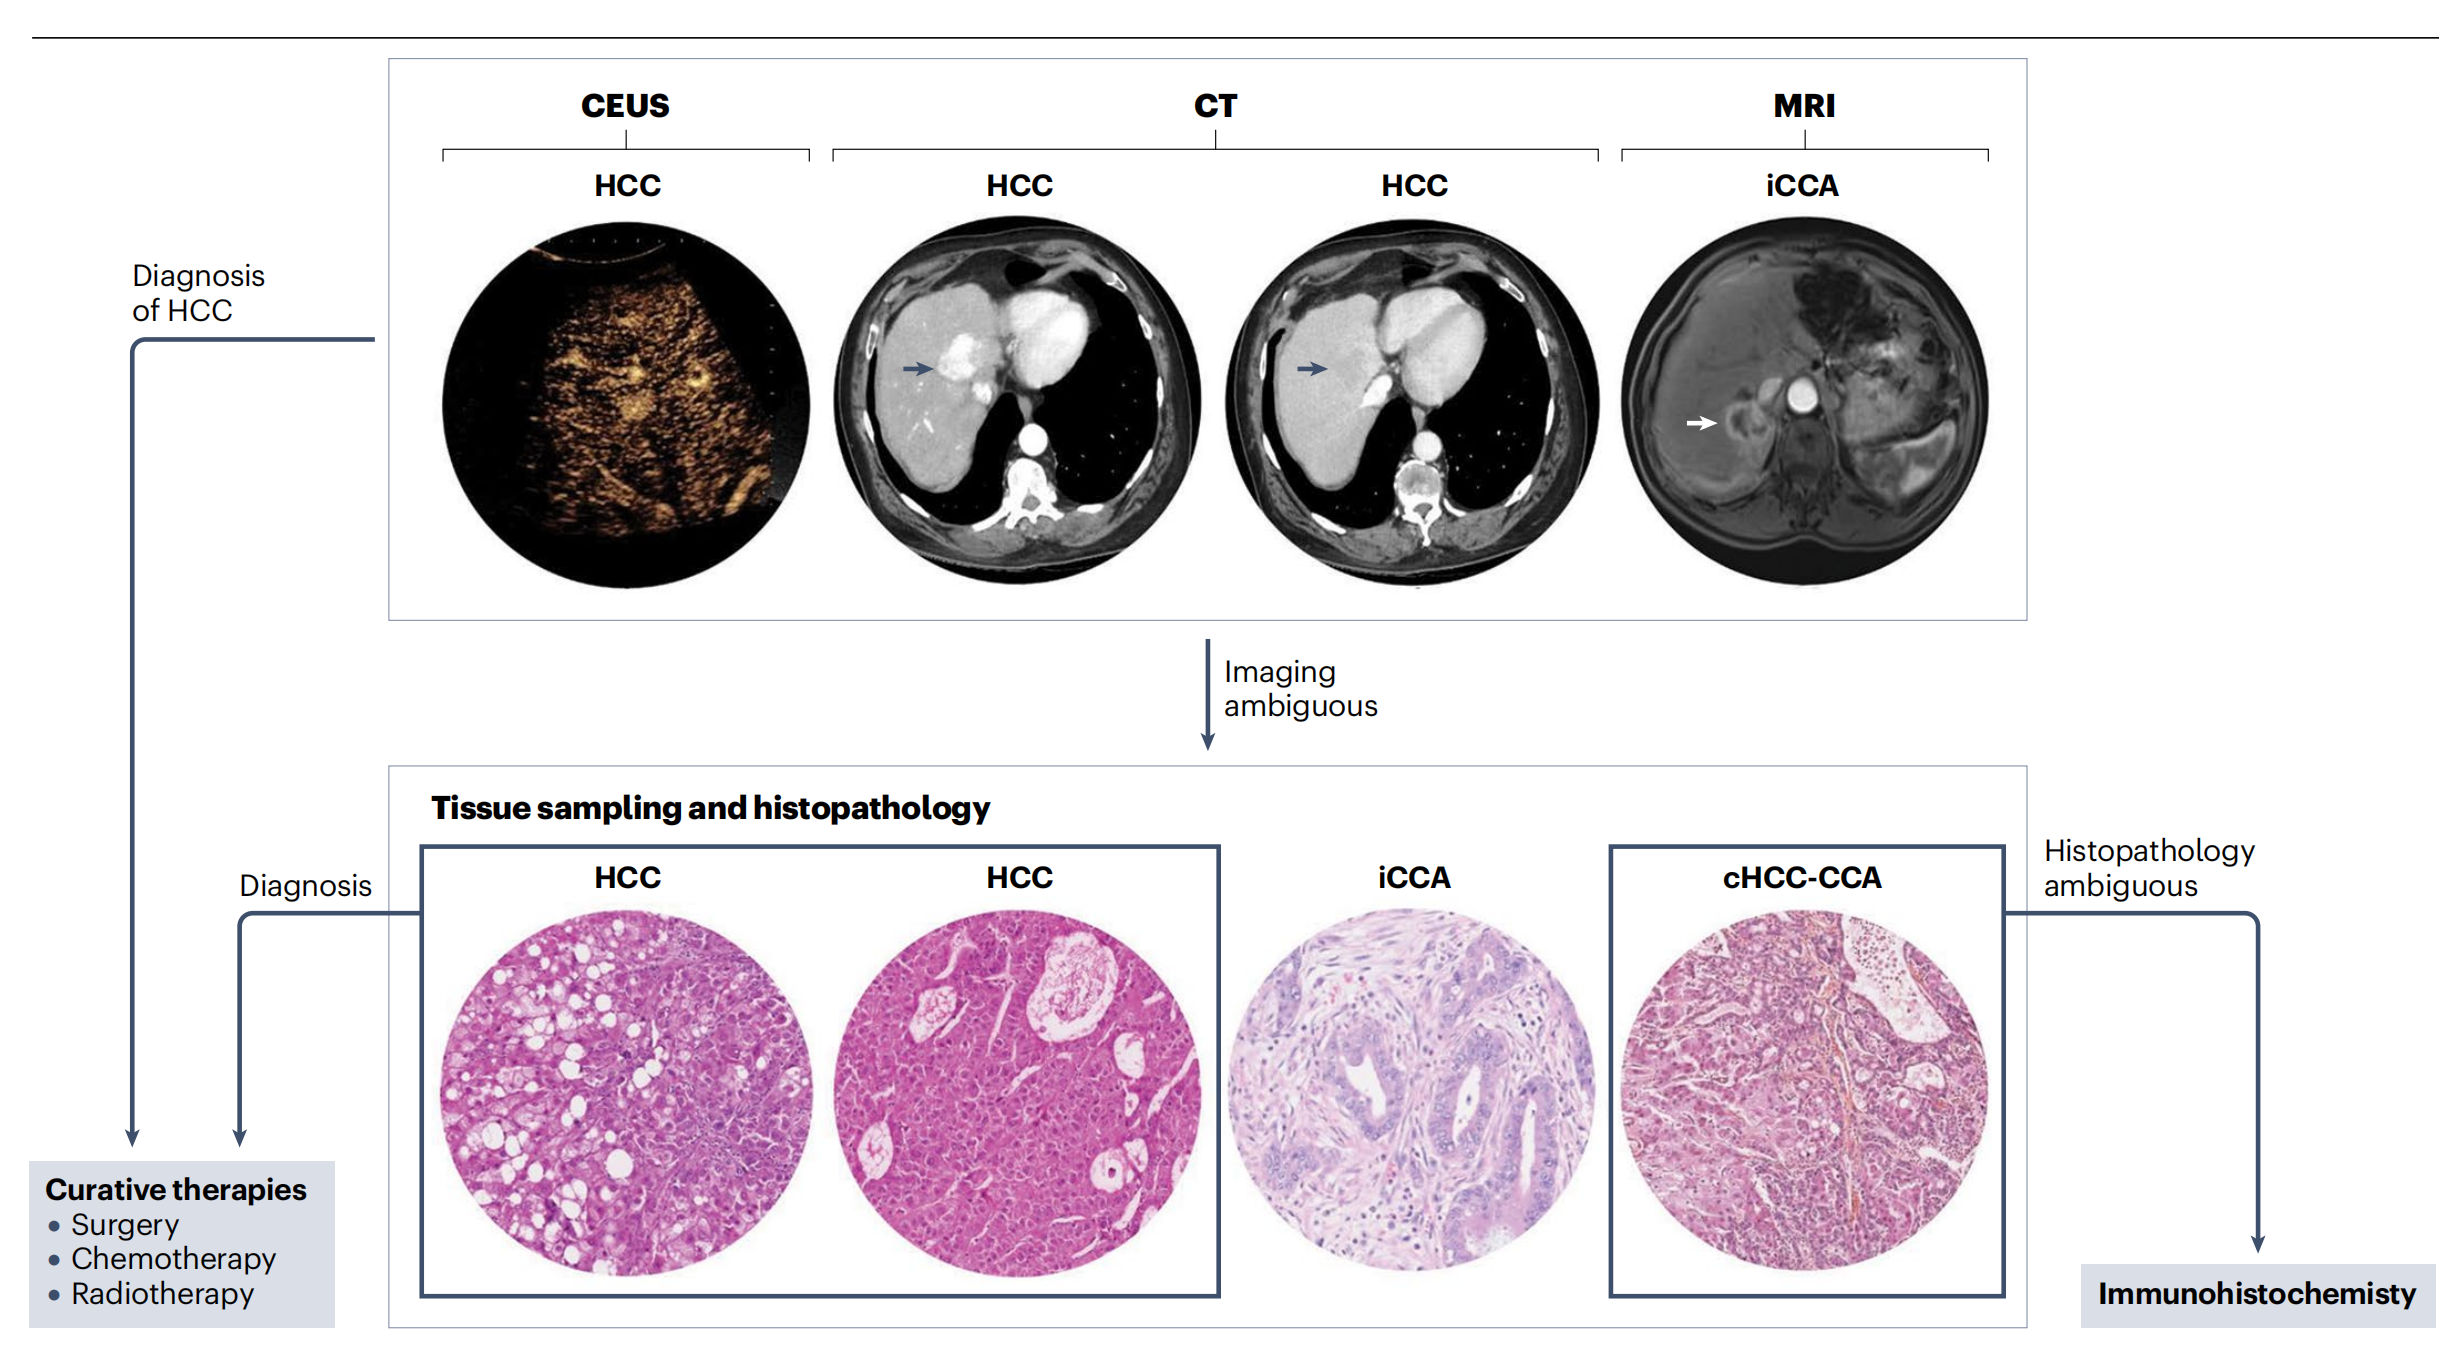

图2提供了原发性肝癌诊断过程中不同影像学检查方法及其后续步骤的概览。

通常首先进行MRI、CT或对比增强超声(CEUS)等放射学成像检查,当影像学结果不明确时,会进行组织病理学评估。

典型的肝细胞癌(HCC)在动脉期(CT扫描,左侧;“wash-in”,蓝箭号)显示高强度增强,在门静脉期(CT扫描,右侧;“wash-out”,蓝箭号)与肝脏其他部分相比显示低信号。肝内胆管癌(iCCA)在动脉期(MRI扫描,白色箭头)显示周边增强。

从组织学角度看,HCC通常表现为具有假腺样结构的微梁状结构,但肿瘤具有高度异质性,其他亚型,如脂肪性肝炎性(HCC组织学,左侧)也得到了广泛认可。iCCA显示肿瘤细胞排列在纤维基质中的腺体内。由于混合性肝细胞-胆管癌(cHCC-CCA)对放射科医师和病理学家来说诊断最具挑战性,因此影像学和常规组织病理学通常需要免疫组化的支持。

分析如下:

- 放射学成像:在肝癌诊断中,首先使用MRI、CT和CEUS等方法进行成像,这些方法可以揭示肝脏中的异常区域。

- HCC的影像特征:肝细胞癌在动脉期呈现快速的血管充盈(wash-in),在门静脉期则相对周围肝脏组织呈现低信号(wash-out)。

- iCCA的影像特征:肝内胆管癌在动脉期显示为周边增强,这有助于其在影像学上的识别。

- 病理学评估:当影像学结果不明确或难以诊断时,会通过组织病理学评估来确定肿瘤类型。

- HCC的组织学特征:HCC在显微镜下通常呈现微梁状结构和假腺样形成,但存在高度异质性,意味着不同区域可能有不同的细胞和结构特征。

- iCCA的组织学特征:iCCA的组织学特征是肿瘤细胞在纤维基质中形成腺体结构。

- cHCC-CCA的诊断挑战:混合性肝细胞-胆管癌在影像学和组织学上都难以诊断,通常需要免疫组化等辅助技术来协助诊断。